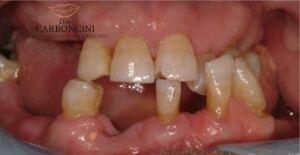

Riabilitazione protesica su impianti in paziente con malattia parodontale

Il paziente aveva perso la maggior parte dei denti a causa della malattia parodontale , e stava perdendo i restanti per lo stesso motivo. Dopo le estrazioni furono inseriti 4 impianti nell’arcata superiore e 4 nell’arcata inferiore seguendo il protocollo del carico immediato.

Restauro protesico finale eseguito con 8 impianti e 22 corone in oroceramica.

PRIMA